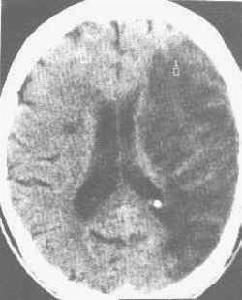

腦梗塞—infarctionofthebrain,動脈阻塞後出現相應部位腦組織的破壞,可伴發出血。發病機制為血栓形成或栓塞,症狀的性質因病變累及的血管不同而異。